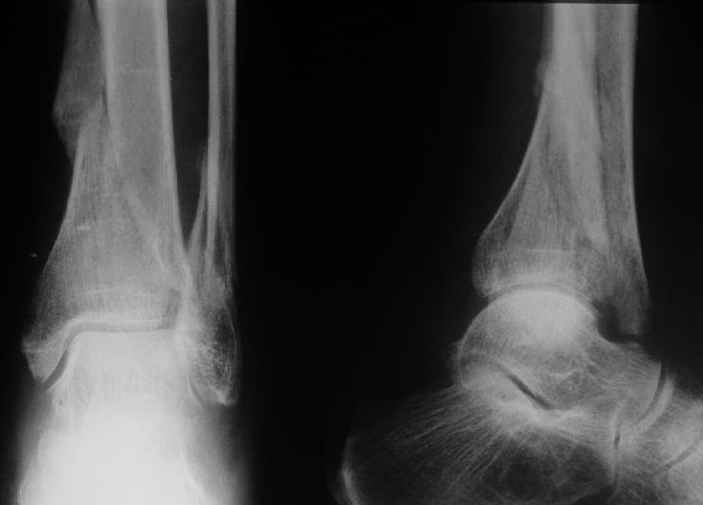

Дама 56 лет 6 недель назад получила спиральные переломы дистальных отделов костей голени. По месту жительства наложили гипс.

Сейчас вот, получается, спохватились. Снимки и КТ в приложении. Какой вариант тут предпочтительнее - открытая мобилизация, репозиция и внутренняя или наружная фиксация? Или ограничиться только резекцией костного шипа над шейкой тарана?Заранее спасибо.A female 56 y.o. 6 weeks ago sustained a fracture of the distal tibia/fibula. At the initial hospital a plaster cast was applied. Now she was referred to our unit. At the moment there is no pain, no obvious mobility. Images and CT attached.What is the best option here? Mobilize the fracture, perform open reduction and internal or external fixation? Or just to cut the anterior spike over the talar neck? THX in advance.

The anterior spike seems to be more antero-lateral, rather than anterior, in such a position that it may not hamper dorsiflexion.

The ankle mortise as a unit is intact.

Отправитель: Андрей 30 Август 2004, 00:44

Судя по рентгену, там вполне приличное сращение.Ось сохранена, укорочение - макс. 1,5 см. Чего ещё хотеть? Шип желатепьно убрать. Исключительно, чтобы